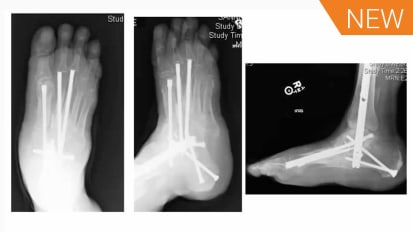

Charcot

External Fixator